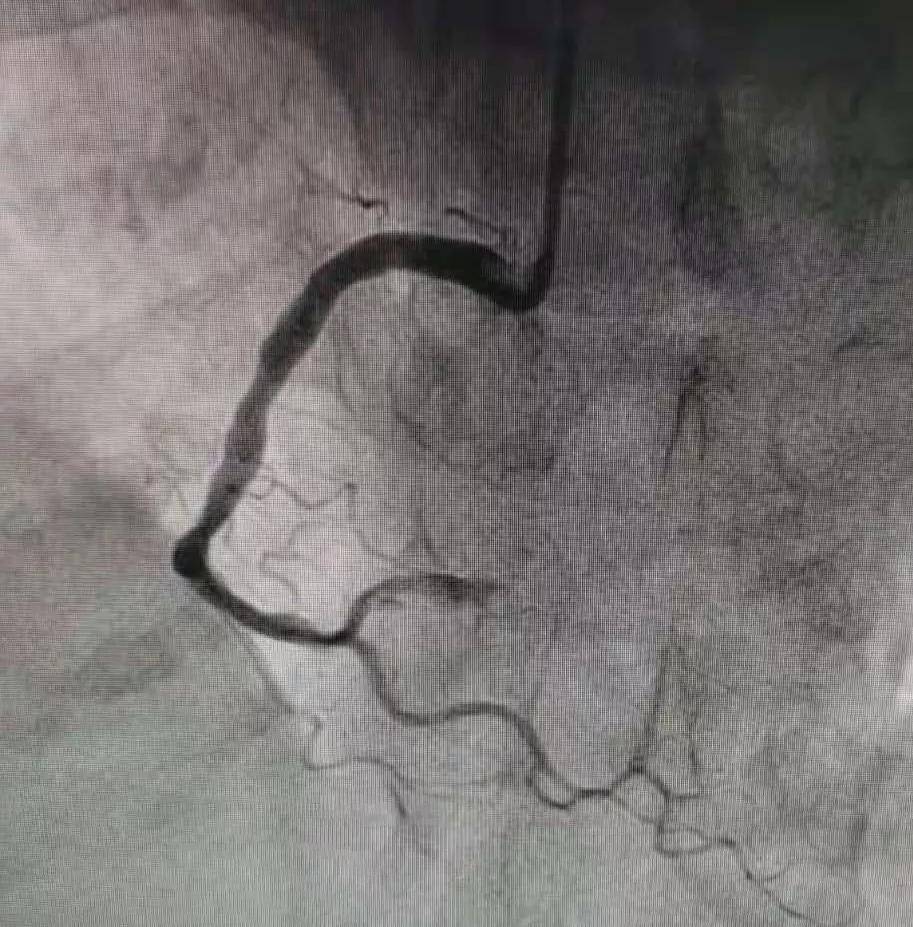

术中冠脉造影提示:患者右冠状动脉远段支架内100%闭塞 , 左冠前降支远端管腔70%狭窄 , 根据患者目前的病情 , 与家属沟通并获得其家属同意后 , 开通闭塞血管 , 给予患者右冠远段支架内药物球囊扩张治疗 , 恢复血流灌注 , 最大程度的挽救了心肌细胞 。